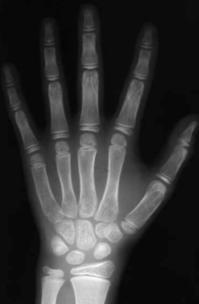

骨龄,就是骨头的年龄,通过拍摄左手正位X线片进行评估,代表骨成熟度和儿童生长发育的潜力,和年龄不一定一致。

就像这样

骨龄是发育年龄,反映人体生物年龄,相较于实际生理年龄,骨龄能更准确评价人体成熟程度。